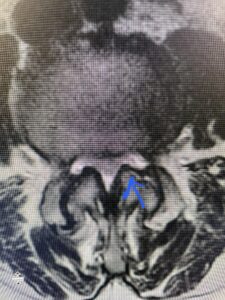

Fig 4: Sagittal T2-weighted lumbar MRI demonstrating L3-4 grade 1 spondylolisthesis with severe stenosis (blue arrow)

Fig 5 Axial T2-weighted lumbar MRI demonstrating significant L3 inferior facet contribution of severe stenosis (blue arrow)